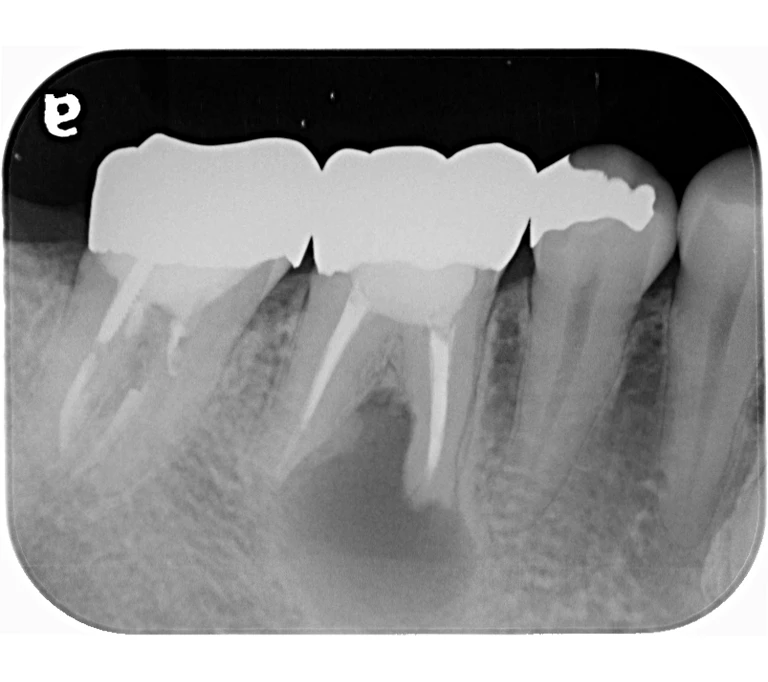

case 3.

治療前

治療後

| 主訴 | 左下奥歯が痛い、歯ぐきの腫れ。 前医で抜歯を提案されたがセカンドオピニオン希望でご来院。 |

|---|---|

| 治療期間 | 約半年(6か月) |

| 治療費 | 約5万円 |

| 治療内容 | 前医ではラバーダム不使用であったため、ラバーダム、マイクロスコープ下にて根管治療を施術。 痛みは消失したが腫れは治らなかったため、意図的再植を行い腫れは消失した。治療後のレントゲンは意図的再植後3年経過したもの。 |

| 治療のリスク | マイクロスコープやCTを使用し、可能な限り精密な根管治療を行っていますが、歯根の形態や病変の大きさ、過去の治療履歴などにより、治癒が得られない場合があります。 また、治療後に再感染や歯根破折が生じることもあり、その場合は再治療や抜歯が必要となることがあります。 治療結果には個人差があり、すべての症例で同様の経過を保証するものではありません。 |